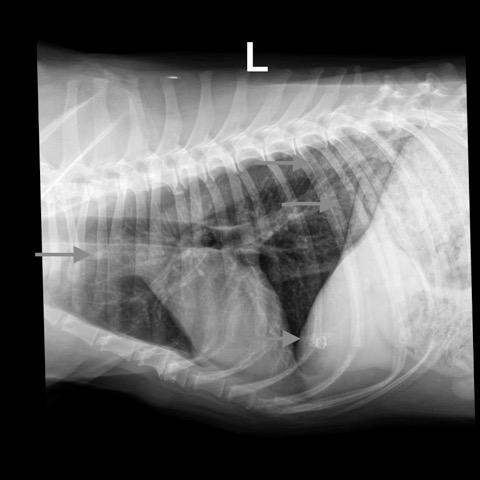

Rads of right lateral, left lateral and VD thorax – Osseous structures: There was mild ventral vertebral endplate modeling within the

mid thoracic spine consistent with spondylosis deformans.

Extrathoracic soft tissue structures: There was a spherical mineral opaque structure

and granulated mineral opaque material superimposed onto the cranial aspect of the

liver and caudal aspect of the lung respectively.

Intrathoracic structures: The course of the trachea was normal. The cardiac silhouette

was small, the caudal vena cava and the pulmonary vasculature were thin.

There was an area of diffusely increased interstitial opacity within the caudodorsal

aspect of the lung.

There also was a generalized bronchial pattern with increased wall visibility and

mineralization.

There was a small soft tissue opaque nodule associated with the cranial lobar vessels

best visible on the left lateral view (see image below)

The findings indicate mild non-cardiogenic (consider neurogenic) pulmonary edema. There was hypovolemia with microcardia and underperfusion of the lung and a chronic bronchial pattern, which may be age related or associated with chronic airway disease. The small nodule is compatible with an end on pulmonary vessel. A secondary neoplastic nodule cannot be ruled out. The mineral opaque material is likely associated with the hepatic biliary system. This is usually benign. Correlate with the chem profile.